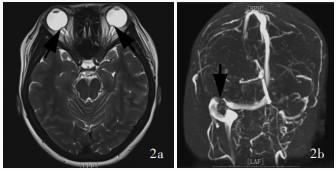

Higgins JN , Gillard JH , Owler BK , Harkness K , Pickard JD . MR venography in idiopathic intracranial hypertension: unappreciated and misunderstood. J Neurol Neurosurg Psychiatry, 2004, 75: 621- 625.

Li BM , Liang YP , Cao XY , Wang J , Liu XF , Yang CS , Wang CM . Image anatomic characteristics and clinical diagnosis and treatment of cerebral venous sinus stenosis. Zhonghua Yi Xue Za Zhi, 2015, 95: 3505- 3508.

李宝民, 梁永平, 曹向宇, 王君, 刘新峰, 杨春水, 王传明. 脑静脉窦狭窄的影像解剖特征与临床诊治的探讨. 中华医学杂志, 2015, 95: 3505- 3508.